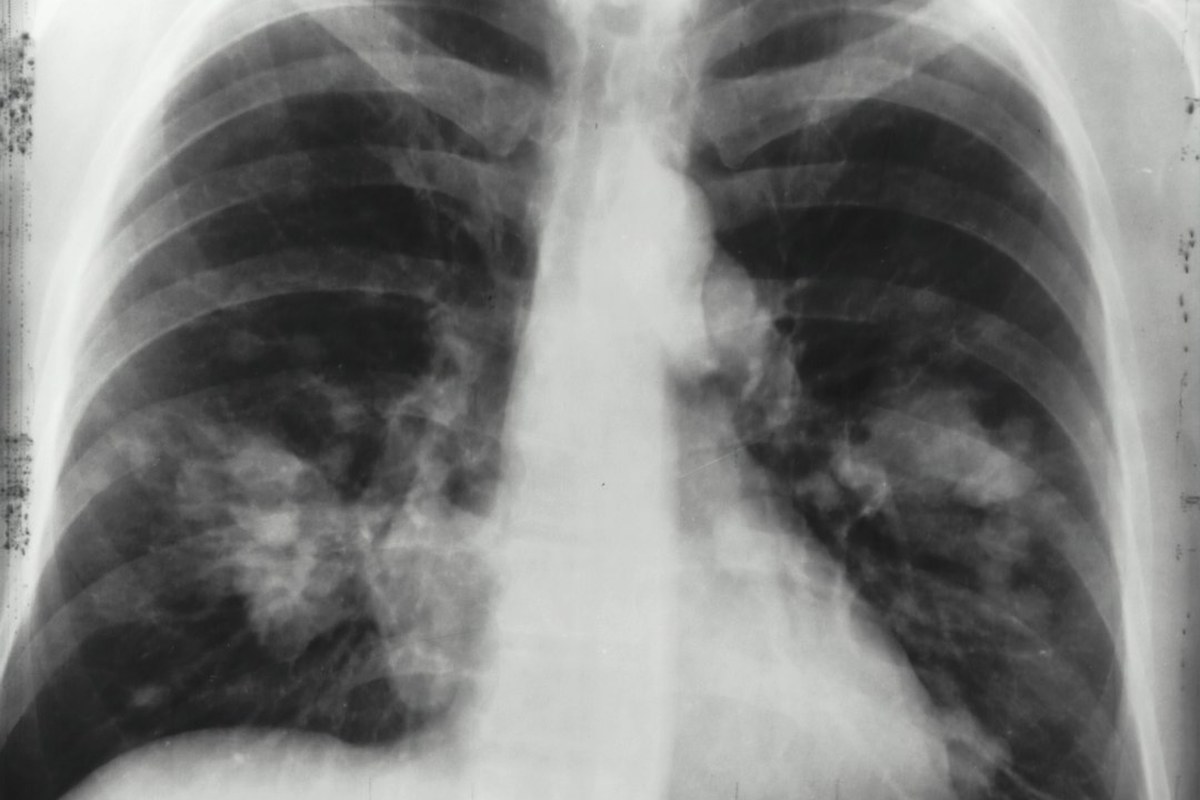

조기 발견이 생명을 좌우합니다 ✅

폐암, 특히 소세포폐암은 조기에 발견하는 것이 무엇보다 중요합니다.

우리나라에서는 54~74세이면서 30갑년 이상의 흡연력을 가진 고위험군을 대상으로 2년에 한 번 저선량 흉부 컴퓨터단층촬영(LDCT) 검진을 시행하고 있습니다. 해당되시는 분들은 꼭 검진을 받으시길 바랍니다.